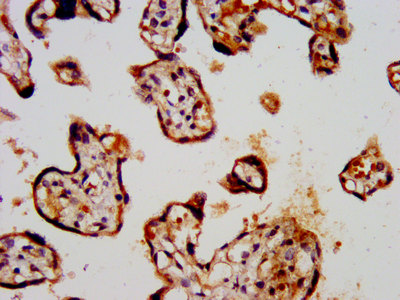

IHC image of CSB-PA012071LA01HU diluted at 1:300 and staining in paraffin-embedded human placenta tissue performed on a Leica BondTM system. After dewaxing and hydration, antigen retrieval was mediated by high pressure in a citrate buffer (pH 6.0). Section was blocked with 10% normal goat serum 30min at RT. Then primary antibody (1% BSA) was incubated at 4°C overnight. The primary is detected by a biotinylated secondary antibody and visualized using an HRP conjugated SP system.